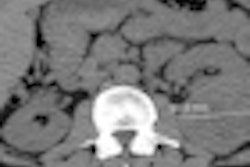

Lung cancer is responsible for more than 160,000 deaths per year in the U.S., and recent studies show that CT screening in high-risk populations can reduce mortality by at least 20%. But physicians, medical societies, Medicare, and private insurance companies are struggling over whom to screen and how to implement recent recommendations. In the LCA's view, screening needs to start now.

The power of CT screening to save tens of thousands of lives a year has been validated along with its cost-effectiveness, and a bill in Congress would bring lung cancer screening into routine clinical use, the LCA said.